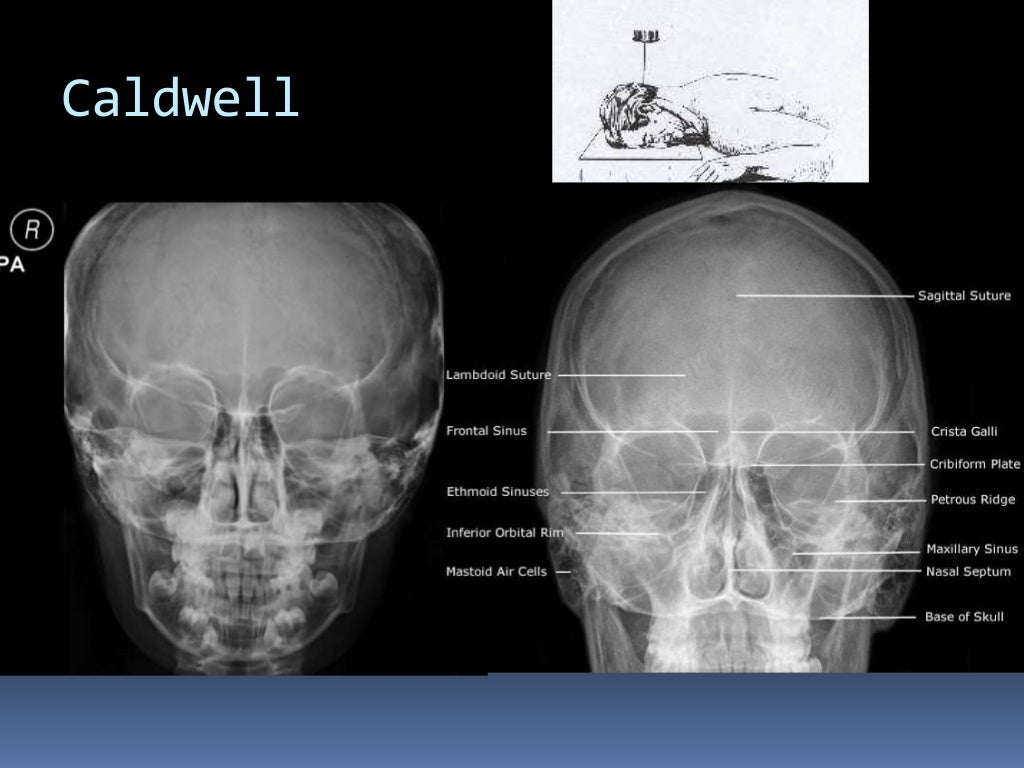

Proyección de Caldwell. La radiografía de Caldwell ( Caldwell's view en inglés) o también llamada radiografía postero-anterior (PA) de senos paranasales, es una proyección radiológica específica para la visualización de los senos frontales y etmoidales. 1 Los pacientes con sospecha de sinusitis frontal (cefalea frontal predominante.

Proyección de Cadwell. Diccionario médico. Proyección radiológica para el estudio del macizo facial, también denominada frontonaso placa, de utilidad en la valoración de los senos frontoetmoidales. QUIERO ESTAR INFORMADO. La información proporcionada en este Diccionario Médico de la Clínica Universidad de Navarra tiene como objetivo.

Citation, DOI, disclosures and article data. The Caldwell view is a caudally angled radiograph, with its posteroanterior projection allowing for minimal radiation to the orbits. This view may be used in imaging of the skull or facial bones depending on the clinical indications.

RX1 CADWELL. La radiografía de Caldwell o también llamada radiografía postero-anterior (PA) de senos paranasales, es una proyección radiológica específica para la visualización de los senos frontales y etmoidales. Los pacientes con sospecha de sinusitis frontal (cefalea frontal predominante) deben ser dirigidamente estudiados mediante.

Proyección de Caldwell Wikiwand

grupos de senos. Proyección PA axial (Método Cadwell): Senos frontales y etmoidales anteriores. Proyección de Waters (Parietoacantial): con boca cerrada: Senos maxilares Proyección de Waters (Parietoacantial) con boca abierta: Senos maxilares y esfenoidales. Proyección Submentovertical: Senos etmoidal y esfenoidal. Centraje: Línea.

Proyección de Caldwell: proyección AP de los senos paranasales en flexión de la cabeza, placa entre. Proyeccion lateral: imagen del plano sagital del paciente. 3. Indicación. -Trauma facial. -Actualmente la radiografía simple de cavidades paranasales no se recomienda para el estudio de sinusitis aguda, ya que su diagnóstico es clínico. 4.

APLICACIONES RADIOLÓGICAS EN LAS CIENCIAS FORENSES Proyección CADWELL ( Para visualizar senos